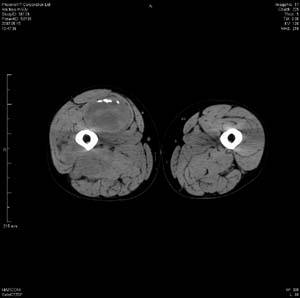

男 63岁 右大腿无痛性肿块11年,x片右大腿软组织肿块影,余无明显异常.ct值-13__239hu

右大腿股内侧股与收肌间隙间多发囊实性占位,界清.内示斑点状钙化.局部骨质无异常.肌肉推压移位表现.

考虑肌间隙病变.可有1,神经来源肿瘤.2,血管来源病变.3,淋巴来源肿瘤.4,脂肪来源肿瘤.5,滑膜来源肿瘤.结合病史只能考虑良性占位.建议增强或mri进一步分析.

同意,病史较长,病变周围分界清晰,考虑良性病变。病灶内有多发斑点状钙化,沿肌间隙生长,血管瘤或淋巴管瘤首先考虑。